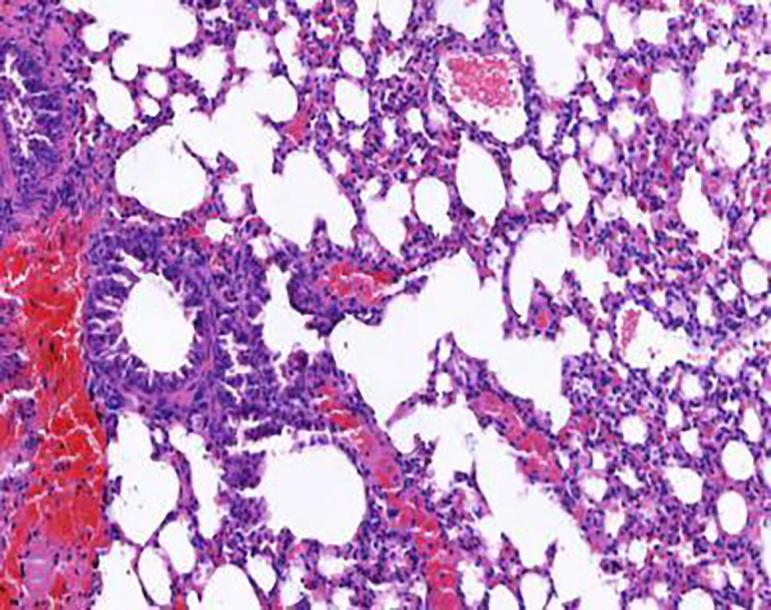

Sixty Kunming mice were randomly divided into normal control group, bronchial asthma model group, low-, middle-, and high-dose syrup groups. Bronchial asthma was induced by injection of ovalbumin combined smoking. Two hours after the last administration, the change of lung function were observed, the contents of NO, IL-6 in serum were detected, the morphological changes of lung and bronchial were also observed, so as to explore the effect of syrup on bronchial asthma mice.

Compared with model group, the Schisandrae Fructus syrup groups can significantly increase the tidal volume of mice and decrease the respiratory frequency and the degree of bronchial stenosis ( < 0.01); The Schisandrae Fructus syrup groups can decrease the levels of NO and IL-6 in serum and improve the pathological changes of lung and bronchus in different degrees.

syrup can significantly improve the biochemical indexes and pathological status of mice with bronchial asthma.